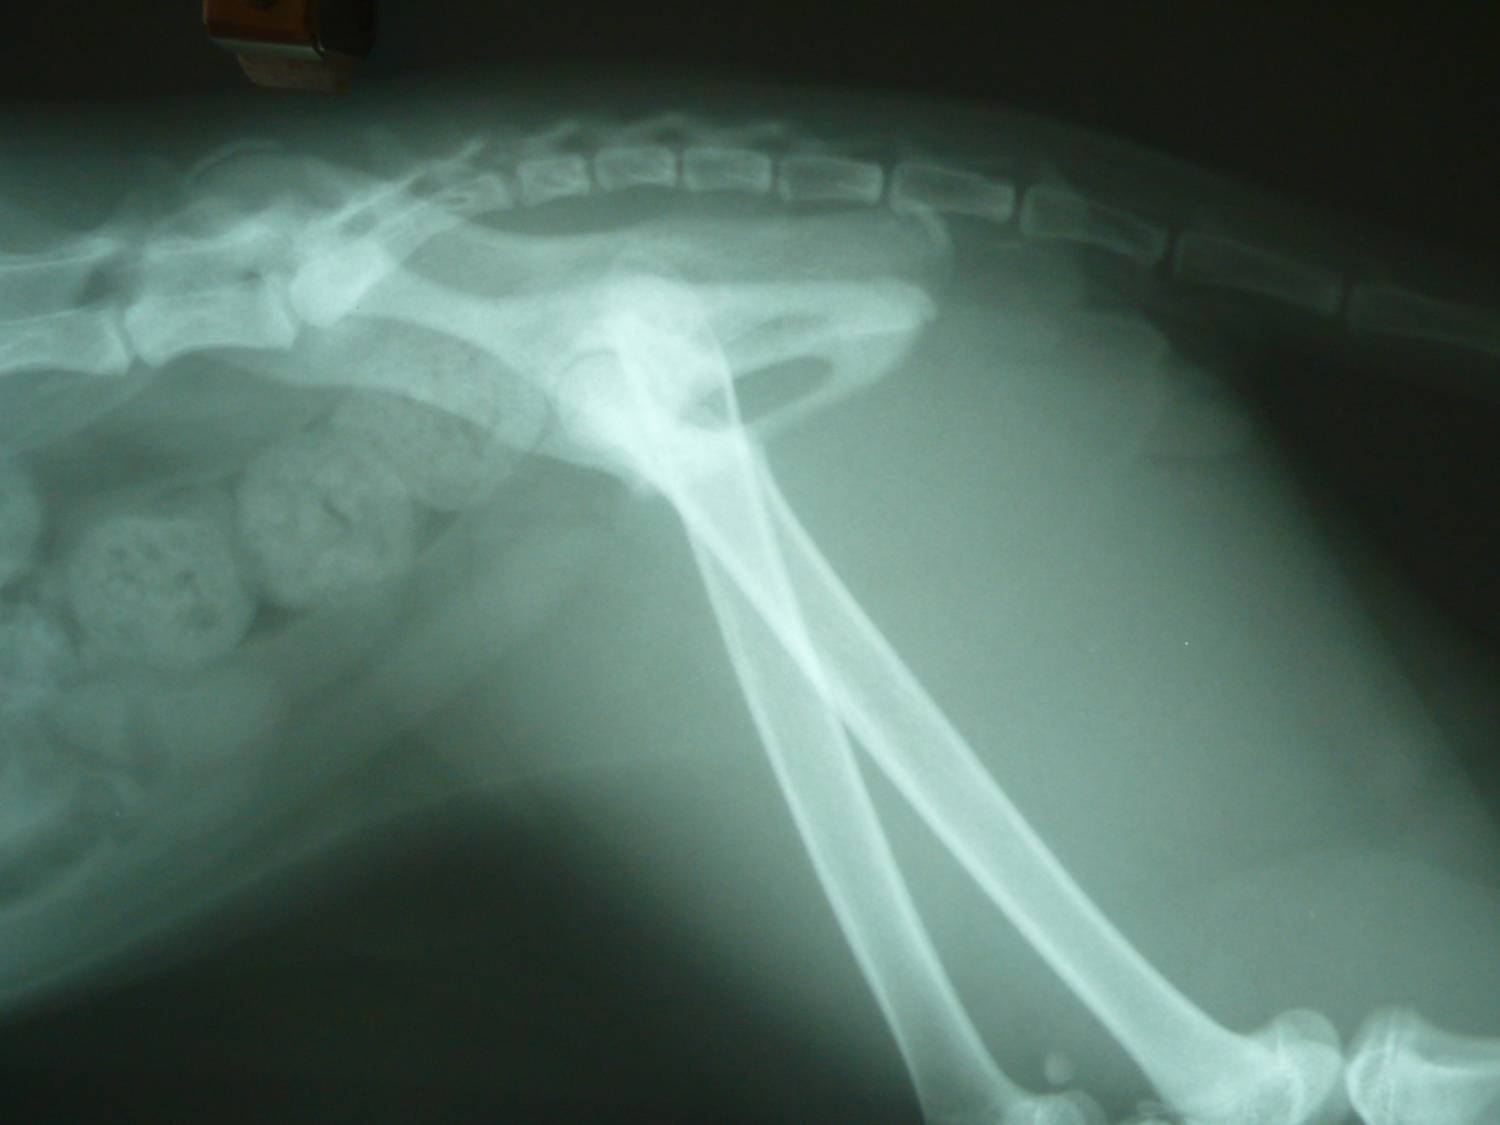

主題: 股骨骨折黑白貓救援 申請者姓名: Akimasa Tu 花色: 申請日期: 2013-01-10 00:10:15 申請者部落格: 申請者臉書網址: https://www.facebook.com/akimasa.tu 所在縣市/合作醫院: 台北市/長沁動物醫院 治療費用: 14700元 需求人數: 16人 已結案 (2013-08-06 13:43:00) 報名人員: Alumi Lu(已付款)、阿麥麥(已付款)、J2(已付款)、Amy(已付款)、Yu-Chen Lee(已付款)、Tsai Wan June(已付款)、Carolyn(已付款)、chiawei(已付款)、收夕(已付款)、何春生(已付款)、黃咪咪(已付款)、Shirley(已付款)、Coco Cheng、鄧伃絜<代馬媽媽捐款)(已付款)、鄧伃絜(已付款)、Tabby Jane(已付款)、洪嘉淑、momo(已付款)、 候補人員: 動物病情說明: 這貓生活在大同區圓環附近的某公園中,某天餵養他的愛媽志工發現,

他無法正常行走,只能三隻腳跳著活動,愛媽電話請我幫忙,貓咪也還

算親人,將他送醫,照X光後發現,原來他的股骨,不明原因骨折了。